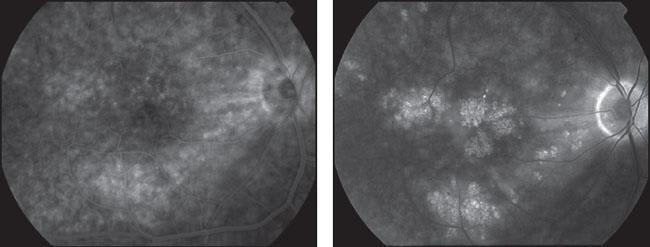

■ Dec. 23, 2004: Fluorescein angiography showed early and diffuse cystic leakage in the macula and disc (Figures 2a and 2b). A sixth sub-Tenon's triamcinolone injection was given. For the next 9 months, vision was stable at 20/40.

Figures 2a and 2b. Prior to implantation of Retisert, fluorescein angiogram of the right eye showing early leakage at 53 seconds and diffuse cystic leakage in the macula and disc at 7 minutes 26 seconds. (Dec. 23, 2004)